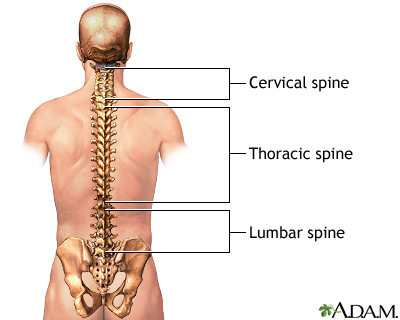

A lumbosacral spine x-ray is a picture of the bones (vertebrae) in the lower part of the spine. This area includes the lumbar region and the sacrum, the area that connects the spine to the pelvis.